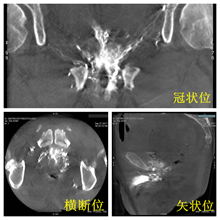

3DCT扫描后可在AW工作站中自动重建,可从冠状位、横断位、矢状位多角度观察前列腺。增强扫描可见前列腺组织明显强化,以此推断超选的动脉为PA。

3DCT扫描重建后前列腺动脉清晰可见   术后3DCT扫描见栓塞良好